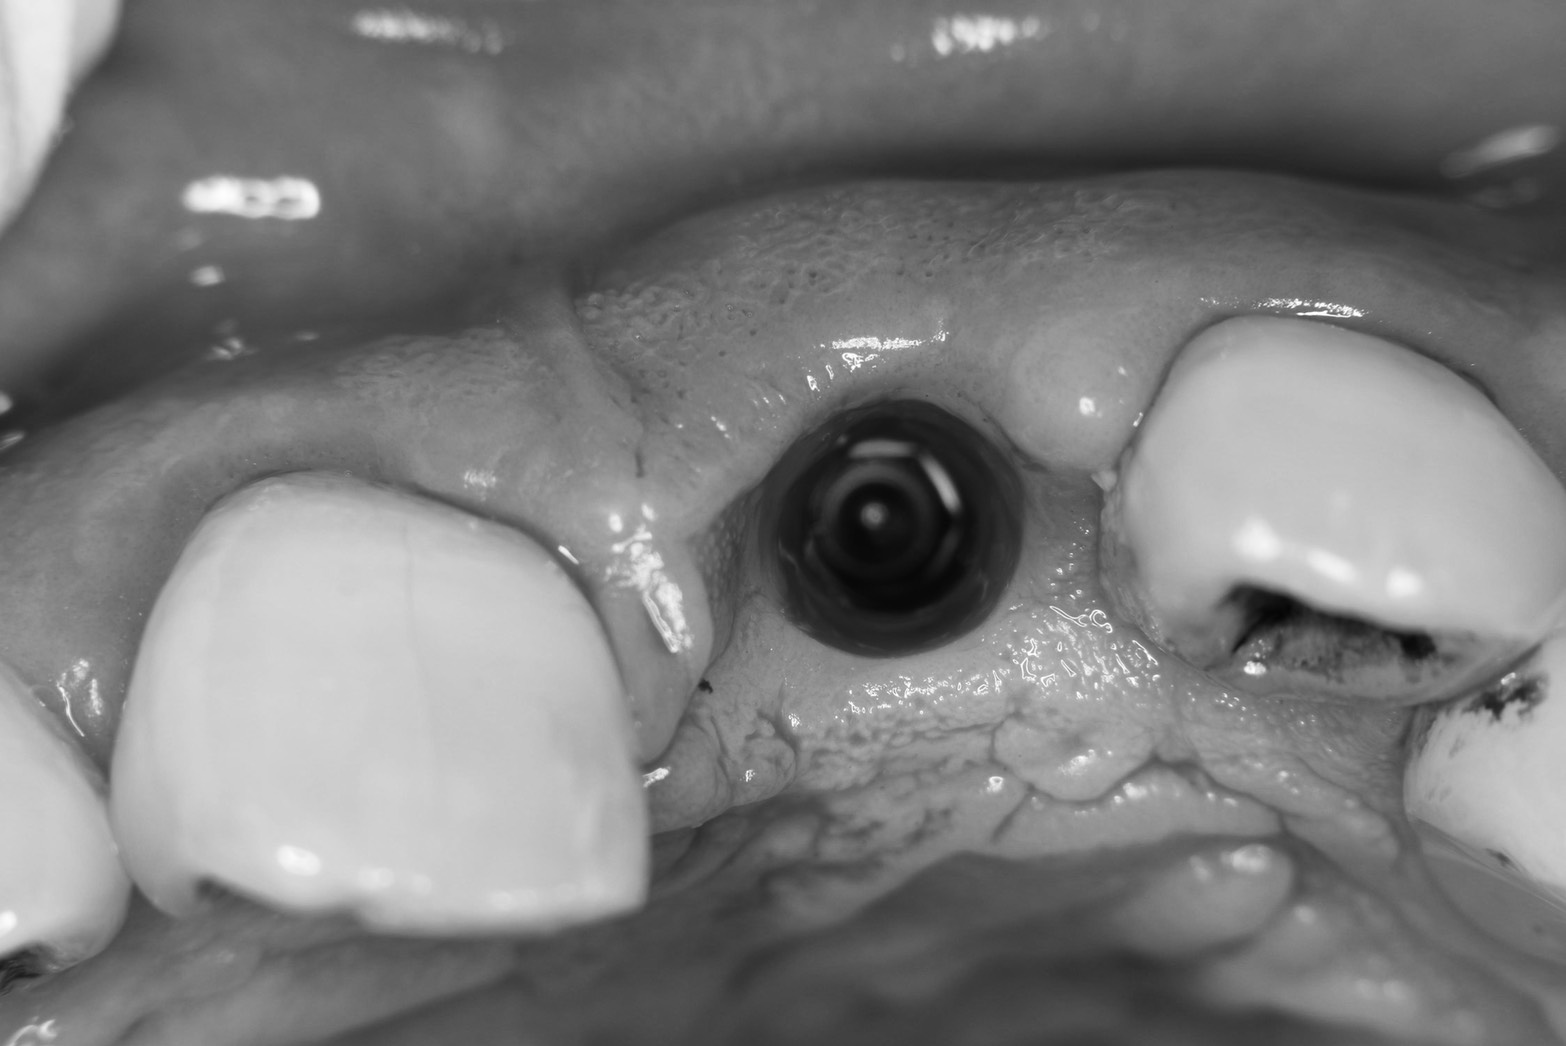

午後には、春にソケットシールド(12/4ブログにテクニックの説明あり)した方の上部構造をセットしました。

狙いどおりにバルコニー、頬側骨板が維持されNICEな結果に(^_^)v